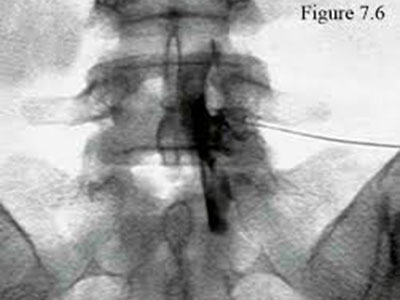

Nucleoplasty

This is a percutaneous procedure to decompress the intervetebral disc thus relief pain and sciatica in patient with slipped disc without doing open surgery.

It uses either radiofrequency energy or plasma light to dissolve the slipped disc nucleus and indirectly decompress the disc and relief the symptoms.

However, careful patient selection is important for an excellent result.

This procedure is indicated for patient who suffers from a contained slipped disc as noted in MRI scan.